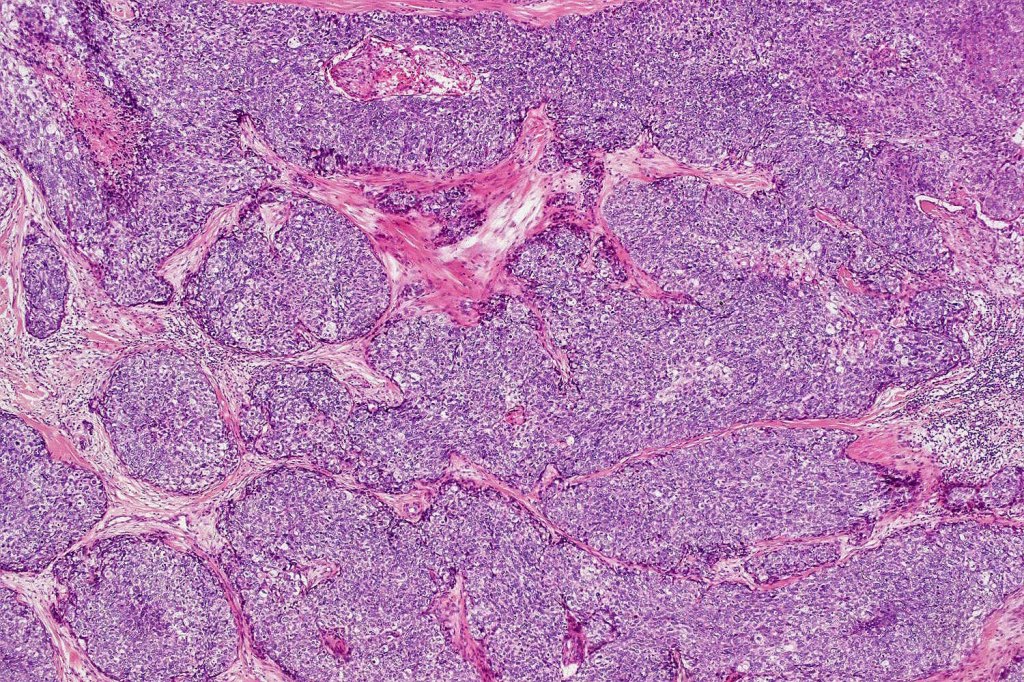

•Well differentiated lobular growth pattern though to a poorly differentiated tumor often showing a diffuse, infiltrating border which may extend into the subcutaneous fat

•Comedo type necrosis commonly present

•Tumors are composed of an admixture of darkly staining basaloid cells with hyperchromatic or vesicular nuclei and more obvious sebaceous cells with eosinophilic, bubbly, multivacuolated cytoplasm frequently indenting the nucleus (scalloped)

•Often mitoses are numerous and abnormal forms evident